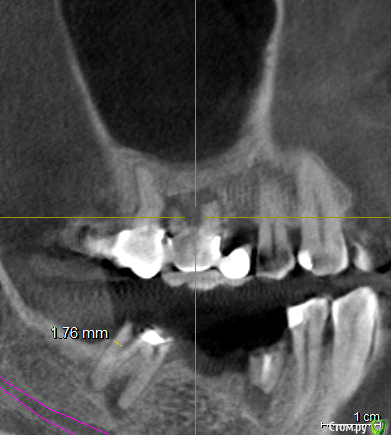

vpaoli Опубликовано 29 февраля, 2016 Поделиться Опубликовано 29 февраля, 2016 (изменено) Посыпались зубы... , что говорят имплантологи-хирурги известно - все удалить и заменить. Хотелось бы получить мнение терапевтов.Под вопросом зубы 16-17, 26-27 и 47. С 45-47 слетел мост, 26-27 после чистки ниткой, у нитки гнилостный запах, над ними в гайморовой пазухе большая киста (видимо как говорят стоматологи онтодогенного происхождения). 47 сидит очень крепко, красноватого цвета, видимо резорцированный и хрупкий. подскажите, можно ли хоть какой то из них лечить?Еще вопрос - над 26, 27 киста в гайморовой пазухе, это опасно или лучше не трогать ? О кисте я узнал только сделав КТ, ранее и сейчас даже не ощущаю ее присутствие.Всех заранее благодарю за высказанное мнение. Изменено 29 февраля, 2016 пользователем vpaoli Ссылка на комментарий

DmitrySH Опубликовано 29 февраля, 2016 Поделиться Опубликовано 29 февраля, 2016 Лучше выложите ссылку на КТ целиком. По данным скриншотам верхние лечить, а нижний 50/50 1 Ссылка на комментарий

faity Опубликовано 1 марта, 2016 Поделиться Опубликовано 1 марта, 2016 Если по этим срезам смотреть, то я бы 1.8, 1.6, 4.5 удалил, остальные лечить 2 Ссылка на комментарий

DmitrySH Опубликовано 1 марта, 2016 Поделиться Опубликовано 1 марта, 2016 Что-то КТ скачалось, но при установке ошибку выдает. По этим скринам, 45 точно удаляется. Это без вариантов. У меня есть некоторые сомнения в 4716 да, возможно удаление, но ракурс не очень удачный. ради него и хотел КТ посмотреть.18. не будет функционировать как зуб.Про мост 47-44 лучше сразу забыть и планировать имплантацию в обл 46, 45. 1 Ссылка на комментарий